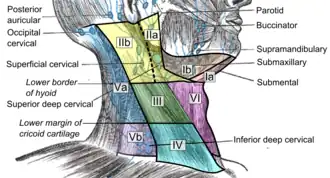

The American Academy of Otolaryngology system (2002) divides the nodes as follows:[1][2][3]

- Level I: Submental and submandibular nodes

- Level Ia: Submental - these are below the mentum of the chin more anteriorly between a triangle formed by the anterior belly of the digastric muscles on each side, and with the hyoid as its base in the axial plane.

- Level Ib: Submandibular triangle - posterolateral to the anterior belly of the digastric muscle between the area formed by its margin, the stylohyoid muscle and the body of the mandible.

- Level II: Upper jugular nodes (Subdigastric nodes) - upper third of the internal jugular vein and adjacent accessory nerve. The upper boundary is the base of the skull and the lower boundary is the hyoid. The anteromedial boundary is the stylohyoid muscle extending between the styloid and hyoid bones, and the posterolateral boundary is the sternocleidomastoid muscle.

- Level IIa: Anteromedial to the vertical plane of the accessory nerve. This nerve is not seen on CT, but correlates to the posterior edge of the internal jugular vein and below the lateral mass of the atlas at the skull base but above the hyoid.

- Level IIb: Deep to the jugular vein and below the lateral mass of the skull base, with its lower margin being the hyoid.

- Level III: Middle jugular nodes - middle third of the internal jugular vein, between the hyoid and cricoid cartilage. They are bounded medially by the sternohyoid muscle and are deep to the sternocleidomastoid muscle. They are also lateral to the internal or common carotid arteries; nodes medial to these vessels are in the anterior compartment of level VI.

- Level IV: Lower jugular nodes - lower third of the internal jugular vein between the cricoid and clavicle, lateral to the sternohyoid and anteromedial to an oblique line drawn between the posterior sternocleidomastoid at the lateral neck and anterior scalene muscle more posteromedially. Similar to level III, level IV nodes are also lateral to the carotid, with nodes medial to this being level VI as well.

- Level V: Posterior triangle nodes - nodes posterolateral to the sternocleidomastoid and anteromedial to the trapezius above the clavicle. The nodes are around the lower half of the spinal accessory nerve and the transverse cervical artery, and include the supraclavicular nodes.

- Level VA: Above the horizontal plane formed by the inferior border of the anterior cricoid arch, including the spinal accessory nodes.

- Level VB: Lymph nodes below this plane, including the transverse cervical nodes and supraclavicular nodes (except Virchow's node which is in IV).

- Level VI: Anterior compartment nodes - Pretracheal, paratracheal, precricoid (Delphian) and perithyroid nodes, including those on the recurrent laryngeal nerve. The upper border is the hyoid, the lower the suprasternal notch, and the lateral borders the common carotid arteries.

The American Joint Committee on Cancer (AJCC) system differs from the above by including Level VII, but the American Academy considered these to be anatomically mediastinal rather than cervical nodes, and therefore should not be included in the classification of neck nodes.[8] However it is based on the 2002 American Academy system, although the boundaries are defined slightly differently.[12]